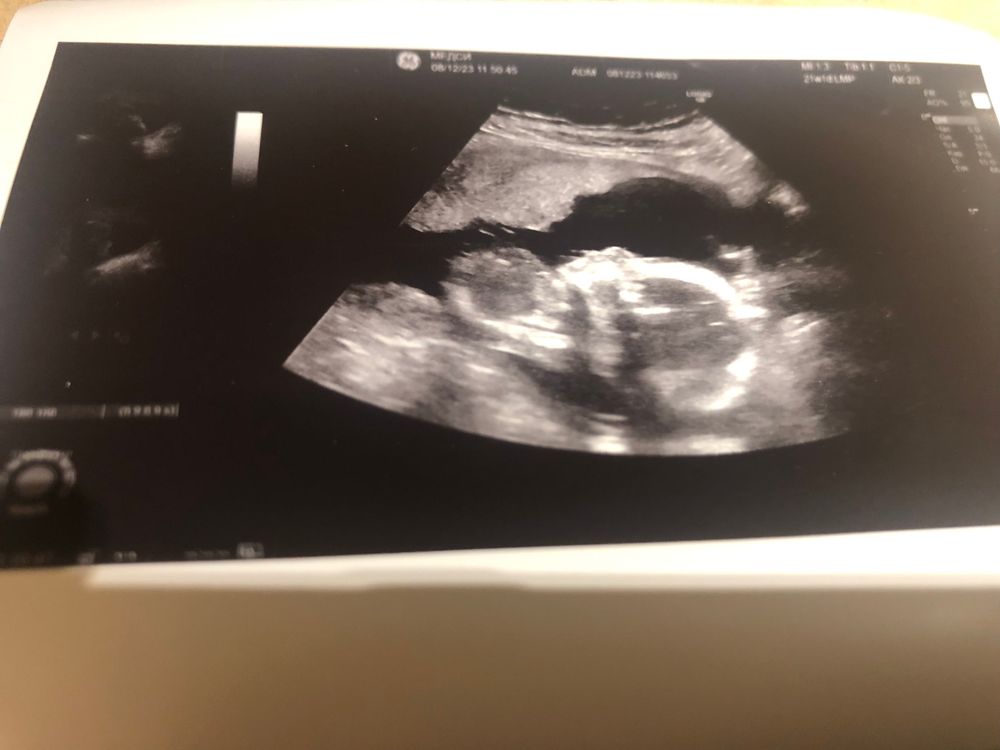

Как настоящий параноик я переделала 2й скрининг в платной клинике. На огромным экране рассмотрела малыша, задала все дурацкие вопросы и получила няшные фотки🤭

Знакомьтесь, пяточка)))

И мой сынок

Прикрепление хориона было низким и перекрывал внутренний зев, теперь плацента поднялась и прикрепление ставят высокое. Все органы и косточки измерили, соответвует сроку🙏 Пузожитель весит 350 грамм и со вчерашнего дня активно ерзает. Голова, да, кругловата, говорят значит в кого-то такая форма🤷🏻♀️